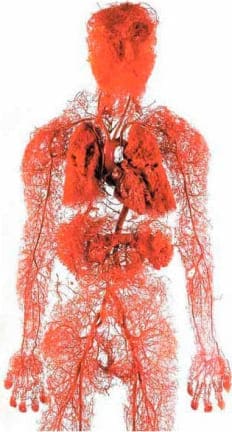

¿Cuál es el órgano más grande del cuerpo humano? Pocas personas lo saben. Incluso los estudiantes de medicina suelen equivocarse. Generalmente dicen que es el cerebro o el hígado. Los más informados dicen que es la piel. Pero en realidad, el órgano más grande es nuestro sistema vascular.

Para ser más claro, la longitud del ecuador de la Tierra es de 40,000 kilómetros. Resulta que la "hilo" de los vasos sanguíneos de una sola persona podría rodear el planeta 2.5 veces.

¿No es sorprendente?

Los vasos no son solo tubos por los que fluye la sangre. Son un órgano complejo y único; cuando fallan, las enfermedades pueden surgir de inmediato.

Los vasos son nuestro sistema de alimentación; la vida misma se mueve a través de los vasos. Si una parte significativa de este sistema está bloqueada, la vida se detiene.

Los vasos obstruidos afectan a todos los órganos.